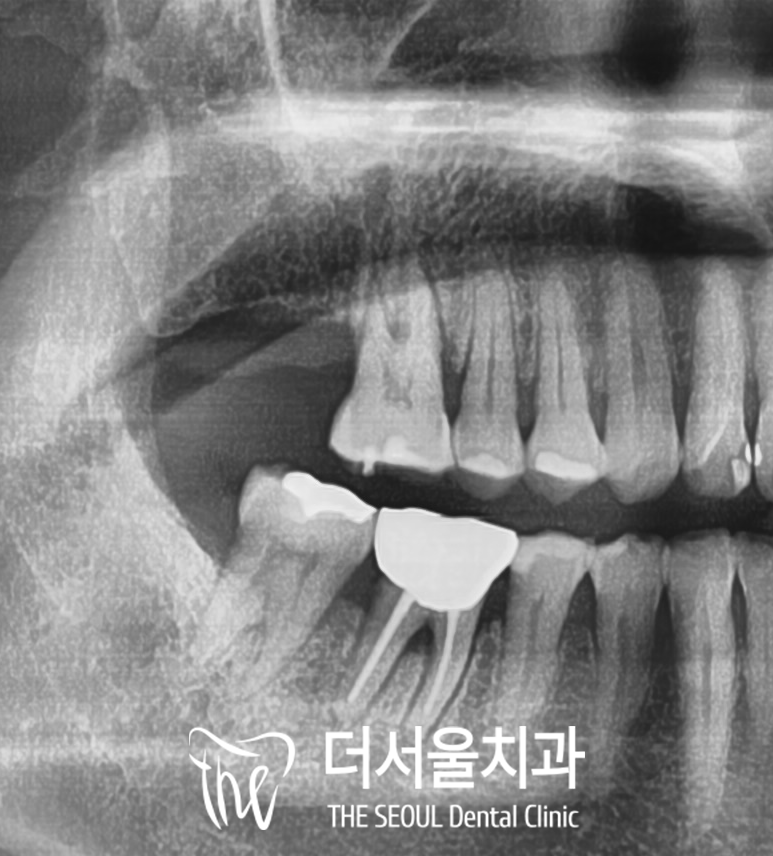

병원에 오게 되면

처음으로 찍게 되는

구강 파노라마 입니다.

자, 이 사진에서 없는 치아가

어디인지 아시겠습니까?

맞습니다!

오른쪽 위 맨 뒤 어금니가 없죠 ?

우리는 그걸 #17, 17번, 제2대구치 같은

여러 가지 이름으로 부르고 있습니다.